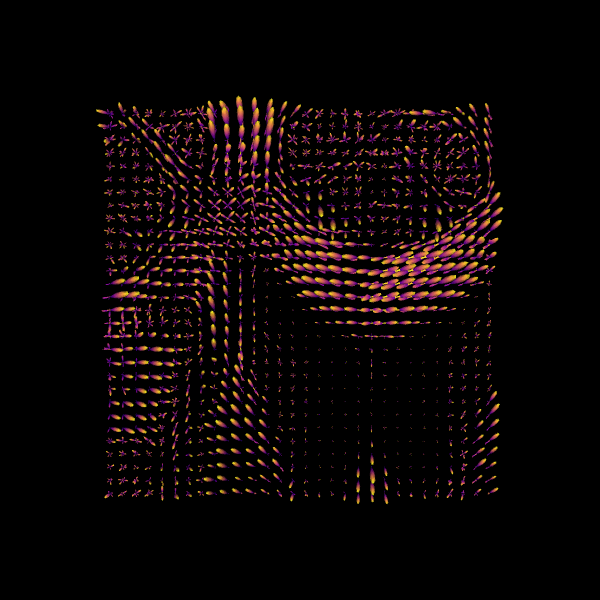

For quality assurance, we can visualize an axial slice from the direction field estimated by the CSA model. Each glyph represents a local fiber orientation derived from the ODF peaks. The underlying ODFs are not shown here.

scene = window.Scene()

scene.add(

actor.peak_slicer(

csa_peaks.peak_dirs[20:50, 55:85, 37:38], peaks_values=csa_peaks.peak_values[20:50, 55:85, 37:38], colors=None

)

window.record(scene=scene, out_path="csa_direction_field.png", size=(600, 600))

Image("csa_direction_field.png")